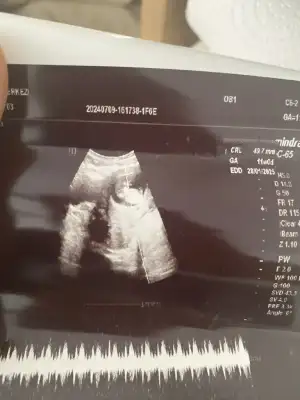

Canım doktorun bir sorun yok dediyse yoktur , telaş yapma hiçHahah oyuncak bebek gibitatlışlar ya inşallah öyledir kuzum biz biraz telaş yaptık plasentaya bağdaş kurmuş asla kıpırdamıyor allahtan nabız var dedi aşırı tepkisiz herşeye ama doktor telaş yaptıracak bişey de demedi bilmiyorum ilk olduğundan herhalde korktuk

Ay bence de çıkıntı falan yok , kız gibi sankiBu arada doktor cinsiyet için daha erken ama şimdilik bacak arasında bir çıkıntı vs görünmüyor dedi. Sizler ne dersiniz kızlar